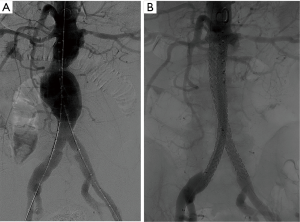

The Nellix endograft (Endologix Inc., Irvine, USA), currently has an FDA Investigational Device Exemption, undergoing efficacy trials, and a European CE mark approval. The device is unique. The sac anchoring endovascular aneurysm sealing system is comprised of two balloon expandable stents that extend in parallel from the non-aneurysmal aorta proximally into the iliac arteries distally. Each balloon expandable stent is surrounded by a polymer filled endobag. The endobags obliterate the aneurysm flow lumen to achieve a seal to resist both lateral and longitudinal displacement forces. Given the filling of the aneurysm sac by the polymer-filled endobag, the device may decrease the incidence of type 2 endoleaks and reintervention rates (Figure 3). In a multicenter study with 171 patients treated with the Nellix device and observed for a median of 5 months (range, 0–14 months), technical success was 99% and type II endoleak rate was 2% (29). There were no aneurysm ruptures or need for open surgical conversion.